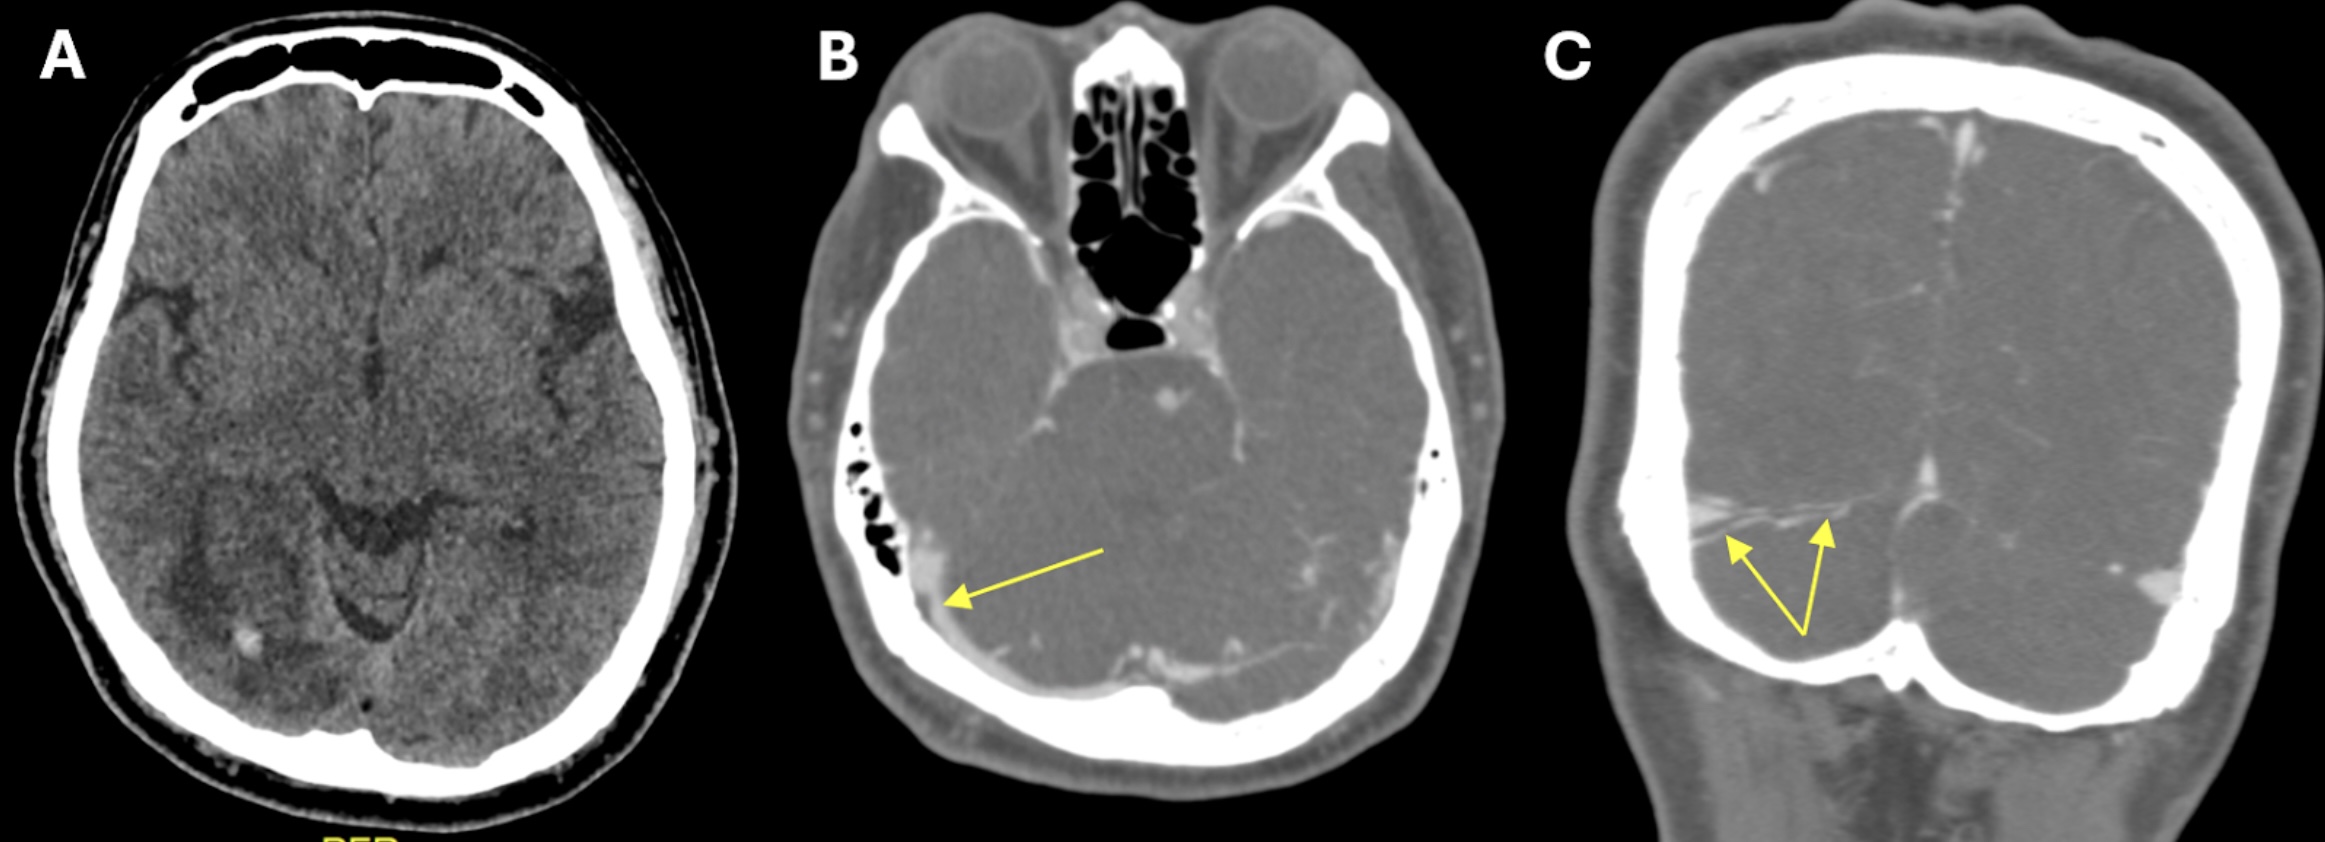

The current COVID-19 pandemic has prompted the development of vaccines to control the spread and severity of SARS-CoV-2. However, there are growing reports of different types of strokes, including ischemic and hemorrhagic strokes, as well as cerebral venous sinus thrombosis (CVST), following COVID-19 vaccination. We presented a case involving a 55-year-old male with a history of ischemic heart disease who exhibited an atypical presentation of visual field impairment one week following Sinovac-CoronaVac COVID-19 vaccination. The patient also experienced mild headache and vomiting for two days preceding the onset of visual symptoms. Right eye’s best-corrected visual acuity was 6/24, and left 6/15. A visual field confrontation test indicated left homonymous hemianopia. An urgent CT venography of the brain documented right transverse sinus thrombosis with occipital haemorrhagic infarct. A nasopharyngeal swab tested negative for SARS-CoV-2, and baseline blood investigations were within normal ranges. The patient was given one week of low-molecular-weight heparin, followed by a three-month course of oral anticoagulant. Post-treatment, there was marginal improvement, although a residual visual field defect persisted. In conclusion, while COVID-19 vaccination remains essential, clinicians must remain vigilant for rare adverse events like CVST and be prepared to manage these cases promptly to ensure patient safety.